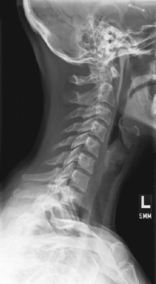

• Erect (sitting or standing) in lateral position, C spine aligned and centered to CR (and centerline of IR)

• Top of IR ≈1-2″ (3-5 cm) above level of EAM

• Raise chin slightly (to remove mandible angles from spine).

• Relax and depress both shoulders evenly (weights in each hand may be necessary to visualize C7).